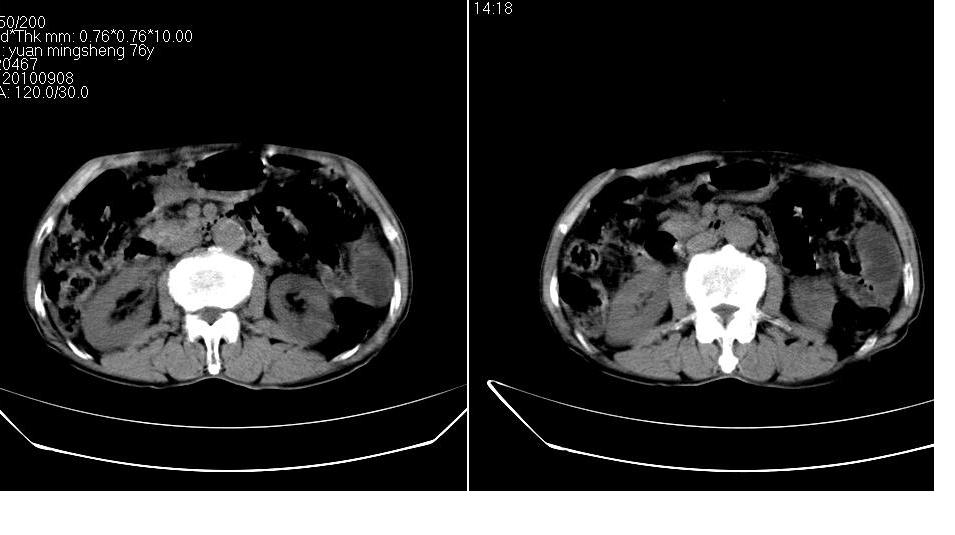

男,76岁,上腹部疼二天来就诊,彩超提示肝左叶占位,随后做上腹部ct平扫,今天做上腹部ct增强扫描,手工推药,效果不好,请谅解。

肝左叶s4肿块强化形式大概是:慢进慢出,逐渐强化----考虑血管瘤/腺瘤?{动脉期应更提前扫}。

肝内胆管积气扩张,胆囊增大,肝右前叶低密度灶,逐渐强化,一元论,胆系感染,局限性肝脓肿;右肾囊肿。

考虑肝s4段肝脓肿可能?未排除肝癌。右肾上极囊肿。